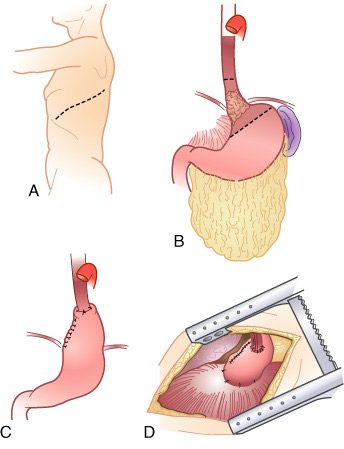

Visualização geral da toracotomia esquerda (A) e mobilização esofágica com tração gástrica (B) para anastomose intratorácica (C). D, É mostrada a anastomose gastroesofágica baixa completa. O estômago remanescente distai foi mobilizado para o tórax através do hiato diafragmático e o estômago é ancorado à faseia pré-vertebral com diversos pontos. A anastomose é confeccionada longe da linha de sutura da transecção gástrica. A borda do hiato diafragmático foi suturada ao estômago para prevenir herniação das visceras abdominais. A incisão diafragmática é fechada com pontos horizontais em U com eversão, seguidos de um chuleio com fio inabsorvível.

Visualização geral de toracotomia direita, (A) com ressecção esofágica, mobilização gástrica (B), e anastomose intratorácica (C) para tumor do terço médio. D, A veia ázigos foi seccionada e o esofago tracionado e dissecado, liberando-se a artéria membranosa traqueal posterior. E, Visão da anastomose gastroesofágica intratorácica no ápice do lado direito do tórax. O fundo gástrico suspenso pela faseia pré-vertebral